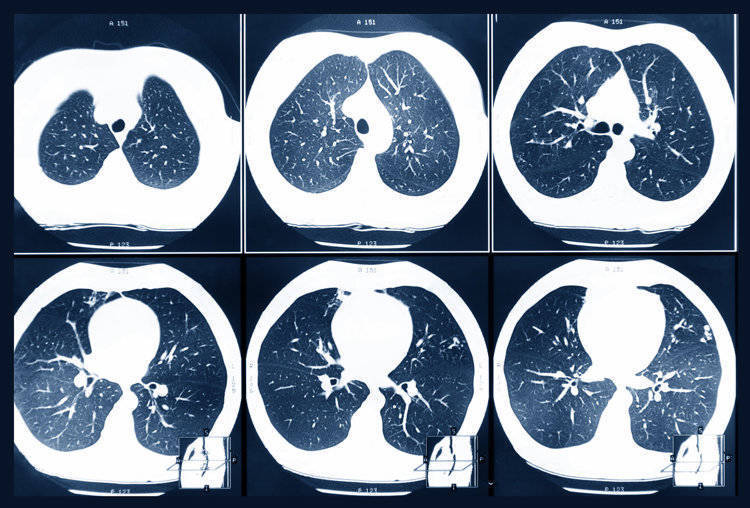

第二天就请假去了医院检查,结果发现结节已经增长到了14mm,且出现了实性成分。后续的增强CT、肿瘤标志物检查高度怀疑是恶性肿瘤,刘先生被安排入院进行相关治疗。好在刘先生的病程还处于早期,可以进行手术治疗,术后他很快就康复出院了。

首先,现在的医学影像技术越来越发达,检查时的分辨率较高,一些隐匿性、之前难以发现的病灶也可以及时发现,这样一来检出结节的几率自然也会增加。

很多患者在罹患肺结节后,身体没有任何不适症状,这种情况下只能通过胸部CT检查来发现结节。

• 变化:在发现结节后,医生会建议定期进行复查,复查过程中发现结节变大或是形态发生了改变,都要警惕可能是恶变了

查出肺结节后不必过于担心,但一定要遵医嘱定期进行复查,复查可及时发现结节的变化,如有恶变倾向也能及时作出处理。